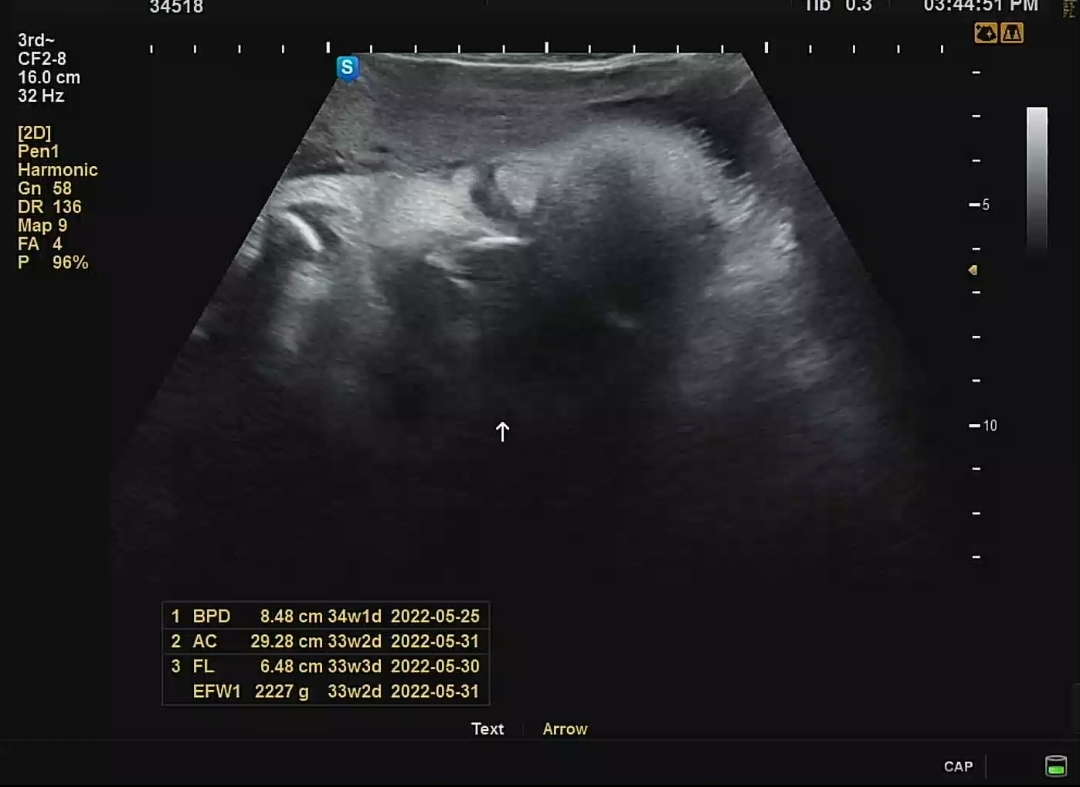

머리둘레는 한달간 주수에 비해 조금 컸었는데, 다시 주수 평균치에 해당하는 크기로 변했었고, 배 둘레, 다리 길이는 주수에 비해 짧긴 했지만 역시나 염려할 정도의 차이가 아니라고 하셨다. 이제껏 체중 불어나는 추이를 봐서 대략 2.1kg 예상했는데 의외로 2.2kg 대를 찍었다. 뿌듯 뿌듯 😉 까꿍이 엄마가 고생이 많다!

차츰 주수가 늘어날수록 초음파 영상에 꽉 차는 까꿍이 모습. 이제는 양수가 줄어들면서 태아가 차지하는 공간이 많아지는 시기기 때문에 더 그러는 것 같다. 제한된 공간에서 손을 웅크리고 있는 까꿍이. 역시나 얼굴보기 힘들었지만 잠깐이나마 가까스로 언 듯 보이는 까꿍이 얼굴이 너무 반갑다.